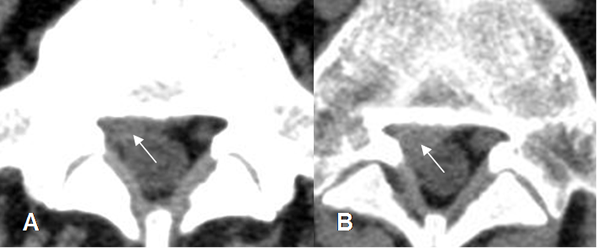

Fig 111. Retracción.

RM axial en T2. Laminectomía derecha, con fibrosis y retracción del saco dural y las raíces hacia la izquierda. (Flechas delgadas). Se aprecia engrosamiento de la raíz derecha. (Flecha gruesa).

Fig 112. Recidiva de hernia.

A: RM axial en T2. Presencia de hernia paramediana izquierda.

B: RM axial en T2. Laminectomía izquierda, con escasa cantidad de líquido. (Flecha gruesa).

Después de un esfuerzo hay reaparición de los síntomas y formación de una nueva hernia, mas grande que la inicial. (Flecha delgada).